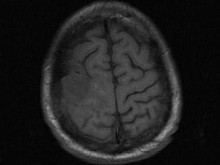

男,63岁,反复抽搐30余年加重伴左侧肢体活动不利活1月余,PE:右顶部约4cm×5cm大小隆起包块质硬,不能活动,右上下肢肌力Ⅴ,左上下肢肌力Ⅳ+,根据所提供图像,最可能的诊断为()

A.右顶骨(付脊索瘤)或称为肌上皮瘤

B.右顶骨转移瘤

C.右顶骨骨瘤

D.右顶骨血管瘤

E.右顶骨胆脂瘤

[单选题]男,63岁,反复抽搐30余年加重伴左侧肢体活动不利活1月余,PE:右顶部约4cm×5cm大小隆起包块质硬,不能活动,右上下肢肌力Ⅴ,左上下肢肌力Ⅳ+,根据所提供图像,最可能的诊断为()A . 右顶骨(付脊索瘤)或称为肌上皮瘤B . 右顶骨转移瘤C . 右顶骨骨瘤D . 右顶骨血管瘤E . 右顶骨胆脂瘤